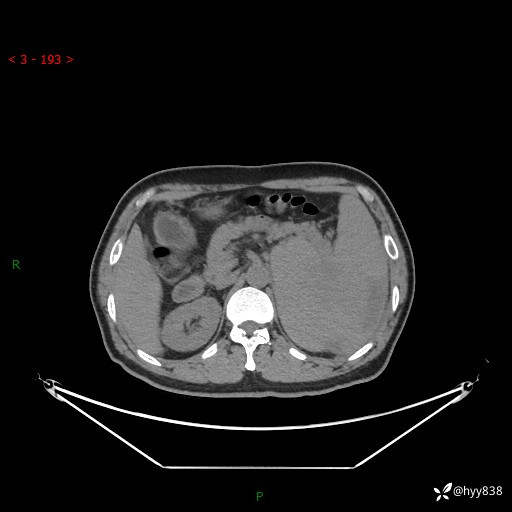

上腹部CT平扫

增强(动脉期+静脉期)